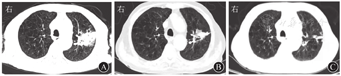

患者男,79岁,因"咳嗽、咳痰8 d,发热3 d"于2020年9月7日收入南京中医药大学附属南京中医院感染性疾病科。患者8 d前无明显诱因出现阵发性咳嗽、咳痰,痰色黄、质黏、难以咳出,伴气喘。3 d前,患者出现发热,最高体温达38.4 ℃,伴大小便失禁及呕吐胃内容物1次,至南京中医药大学附属南京中医院急诊科就诊。查血常规示白细胞计数为23.70×109/L,中性粒细胞比例为0.913,血红蛋白为134 g/L,血小板计数为210×109/L,CRP为73 mg/L。胸部CT检查示两肺气肿伴肺大疱形成,两肺间质性改变;左肺上叶团片影,考虑炎性病灶可能(图1A)。患者既往有心房颤动、心功能不全、慢性阻塞性肺疾病病史;有未分化结缔组织病病史1年余,长期服用泼尼松和雷公藤,泼尼松用量为5 mg/次,2次/d。入院后体格检查:体温为36.5 ℃,心率为75次/min,呼吸为20次/min,血压为98/62 mmHg(1 mmHg=0.133 kPa)。神志清楚,精神萎靡,淋巴结未及肿大。桶状胸,双肺呼吸音减弱,双下肺可闻及少量细湿啰音。心律不齐,未闻及病理性杂音。腹软,无压痛及反跳痛。双下肢无水肿。实验室检查示CRP为160 mg/L;ESR为102 mm/1 h;降钙素原为11.54 μg/L;脑钠肽为2 684 ng/L;铁蛋白>1 650 μg/L;白蛋白为19 g/L;EB病毒、CMV、β-D-葡聚糖试验、半乳甘露聚糖抗原试验、T细胞亚群、免疫五项(IgA、IgG、IgM、补体C3、补体C4)检查、T-SPOT.TB和PPD结果均为阴性。一般细菌痰涂片、痰涂片找抗酸杆菌、真菌涂片检查结果均为阴性。结合既往病史、辅助检查,考虑肺部细菌、真菌感染均不能排除,故予比阿培南(300 mg/次,4次/d)联合伏立康唑(200 mg/次,2次/d)静脉滴注抗感染治疗。9月14日(入院第8天)患者体温恢复正常,咳嗽、咳痰较前好转,胸部CT检查示肺部病灶较前吸收(图1B),血培养结果为乔治教堂诺卡菌阳性(图2),加用复方磺胺甲噁唑(磺胺甲噁唑/甲氧苄啶,800 mg/160 mg, 2次/d)。9月18日完善腹部和头颅MRI检查,结果回报左侧颞叶异常信号,考虑脓肿可能(图3A),余脏器未见血行播散病灶。患者感染乔治教堂诺卡菌,血行播散至脑形成脓肿,播散性诺卡菌病诊断明确,改用头孢曲松(2 g/次,2次/d)静脉滴注联合复方磺胺甲噁唑(2次/d)口服抗感染治疗1周后复查,血常规示白细胞计数为5.90×109/L,中性粒细胞比例为0.821,CRP<1 mg/L。患者临床症状和炎症指标较前明显好转,9月30日出院后序贯口服复方磺胺甲噁唑(2次/d)联合利奈唑胺(600 mg/次,2次/d),治疗10 d后复查血培养结果为阴性,10月14日复查头颅MRI示脑脓肿较前吸收(图3B)。10月27日复查头颅CT,提示病灶较前明显好转(图4)。2021年2月19日患者复查血培养结果为阴性,胸部CT检查示病灶较前吸收(图1C),头颅MRI检查示病灶已吸收完全,予复方磺胺甲噁唑减量(磺胺甲噁唑/甲氧苄啶,400 mg/80 mg, 3次/d)。

诺卡菌繁殖速度较慢,一般需1周才可见菌落,传统方法培养时间不足易造成漏诊,本例患者血培养阳性也是于检测1周后才得到结果,所以选择快速而准确的诊断方法至关重要。目前齐-内(Ziehl-Neelsen)染色联合宏基因组学第二代测序、PCR都被认为有利于提高诺卡菌病诊断的效率及准确性[10,11]。